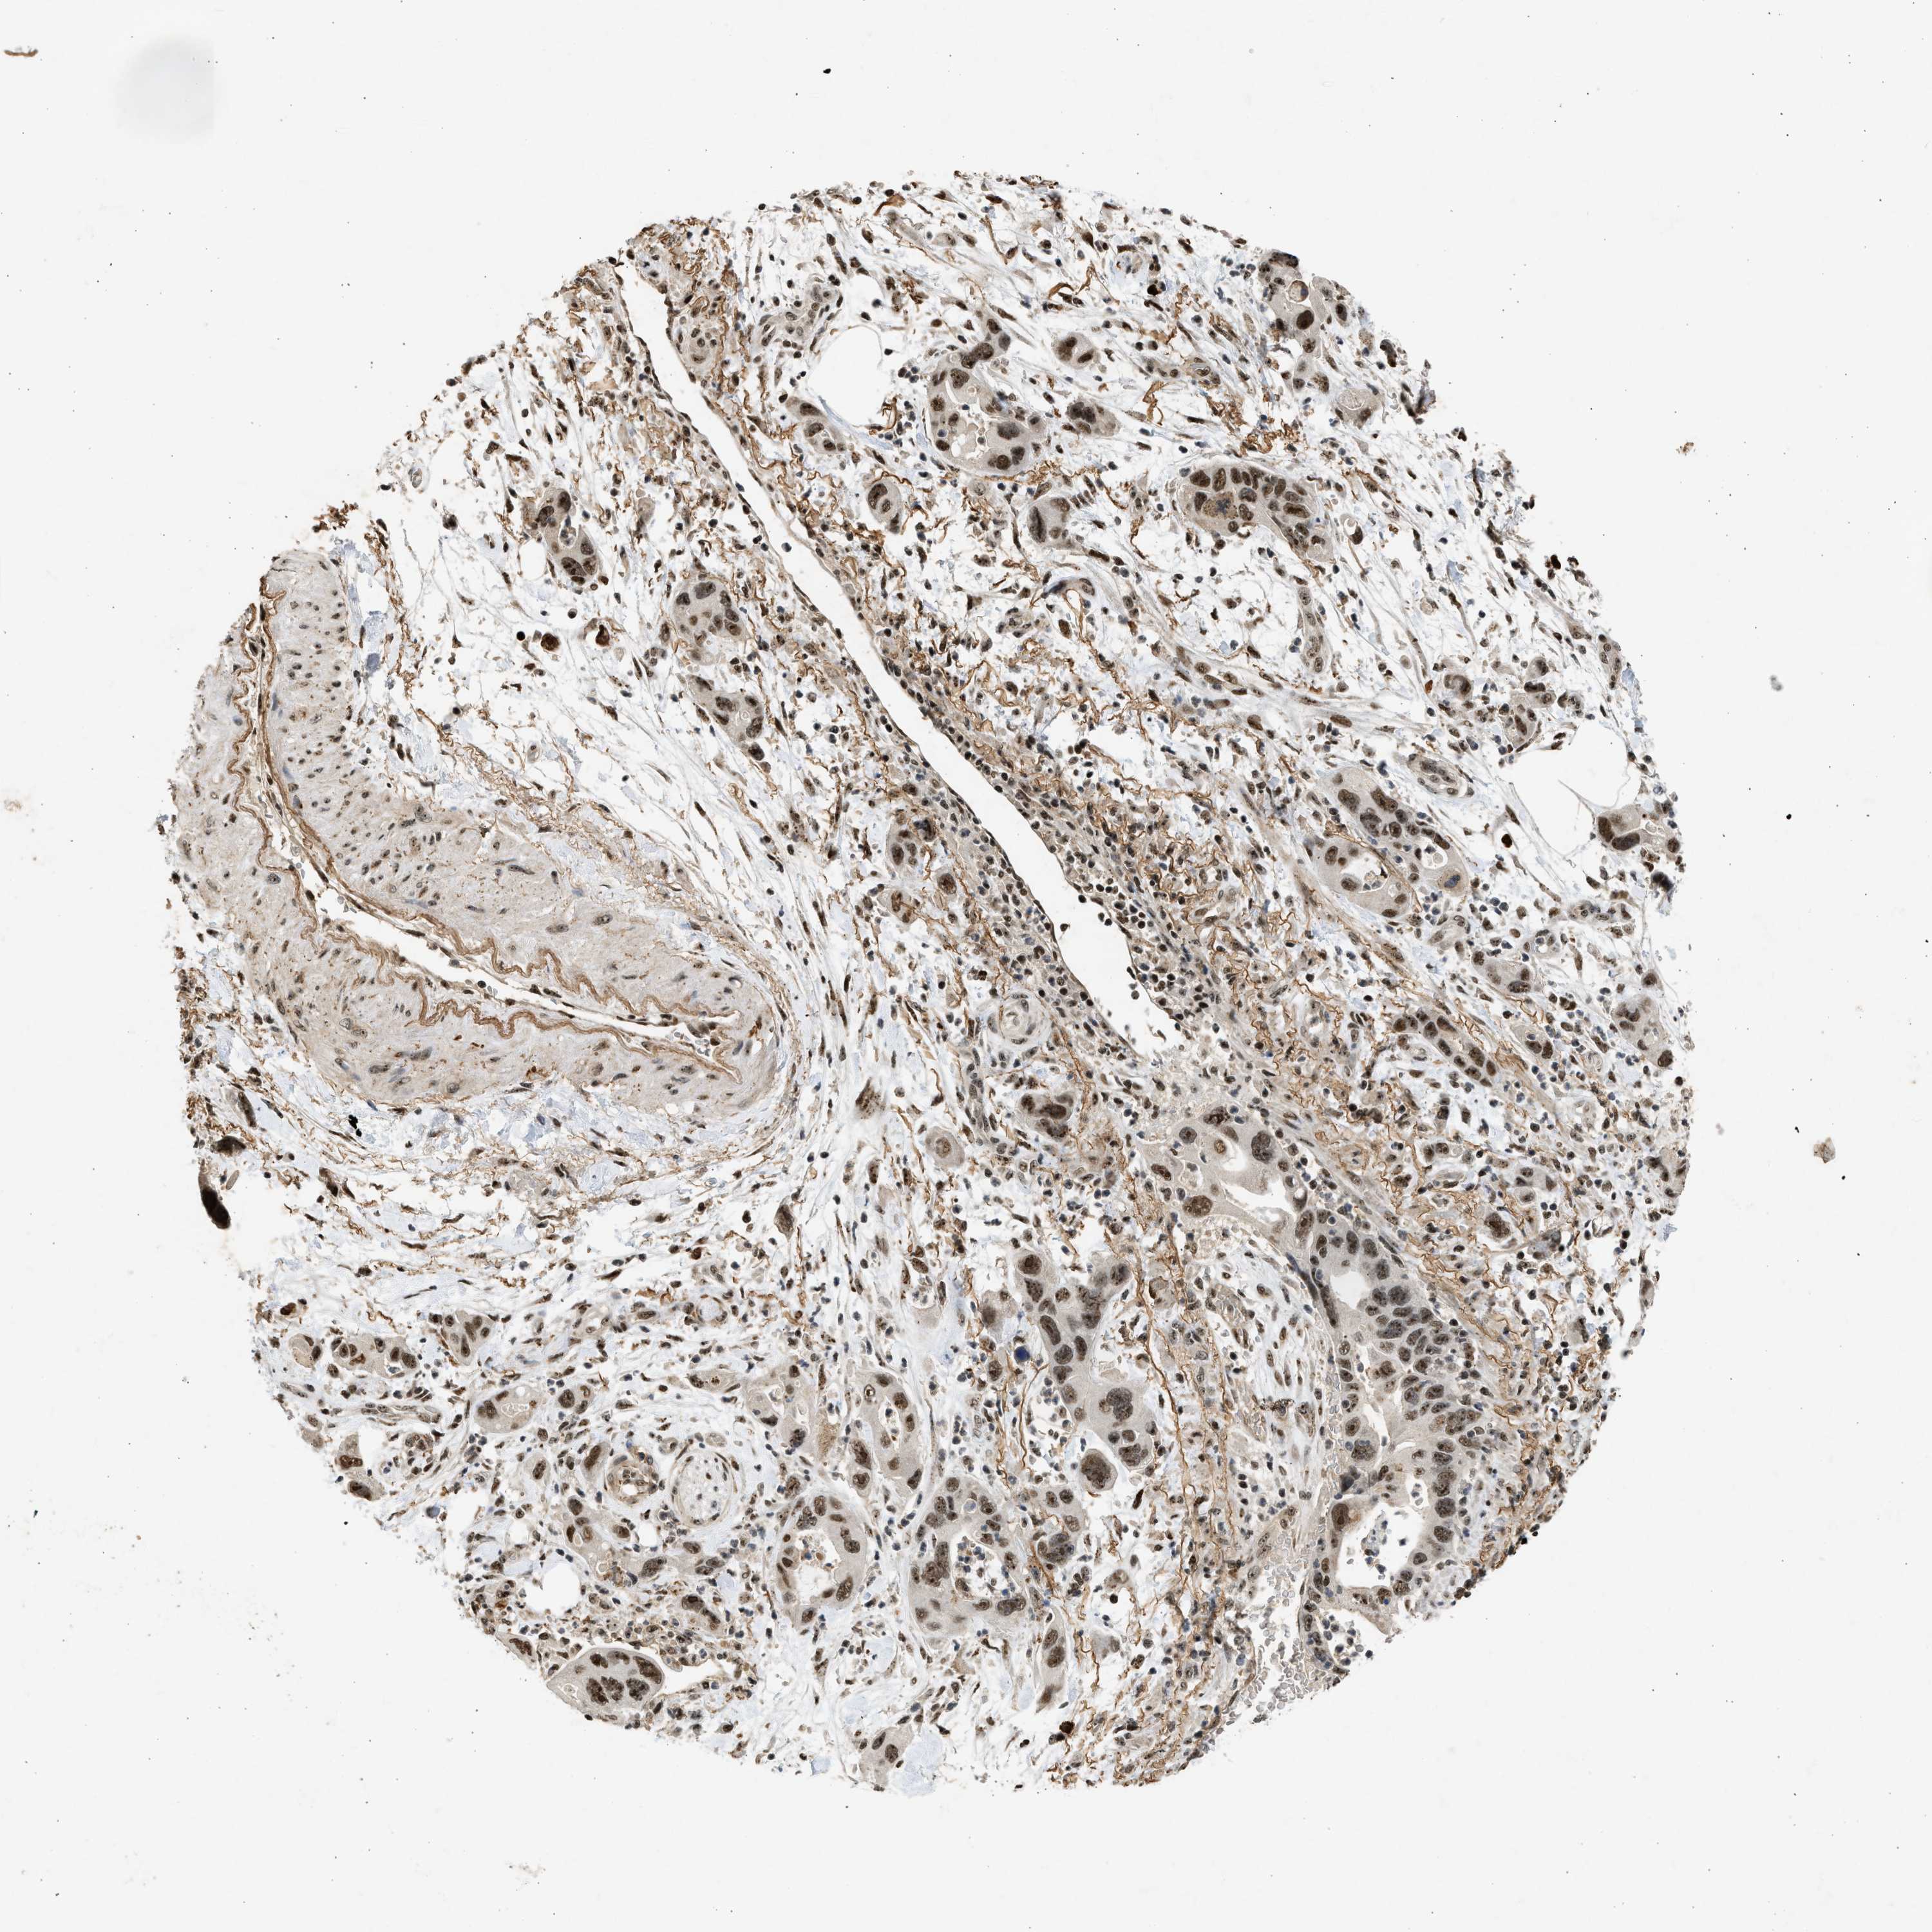

PANCREATIC CANCER - Protein expressioni

A mouse-over function shows sample information and annotation data. Click on an image to view it in a full screen mode. Samples can be filtered based on level of antibody staining by selecting one or several of the following categories: high, medium, low and not detected. The assay and annotation is described here.

Note that samples used for immunohistochemistry by the Human Protein Atlas do not correspond to samples in the TCGA dataset.

Antibody stainingi

Antibody staining in the annotated cell types in the current human tissue is reported as not detected, low, medium, or high, based on conventional immunohistochemistry profiling in selected tissues. This score is based on the combination of the staining intensity and fraction of stained cells.

Each image is clickable and will lead to virtual microscopy that enables deeper exploration of all samples and also displays staining intensity scores, fraction scores and subcellular localization as well as patient and tissue information for each sample.

Antibody CAB018396

Staining

High

Medium

Low

Not detected

Intensity

Strong

Moderate

Weak

Negative

Quantity

>75%

75%-25%

<25%

None

Location

Nuclear

Cytoplasmic/membranous

Cytoplasmic/membranous,nuclear

Adenocarcinoma, NOS